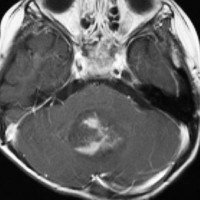

7歳児の小脳半球にある標準リスクの髄芽腫です。画像を一見すればこの髄芽腫は治るであろうと予測します。

手術で完全摘出し,退形成性髄芽腫の病理診断で,脳脊髄照射と局所照射54グレイ,シスプラチンベースの化学療法を6コース加えましたが,半年後に激しい播種再発を生じました。